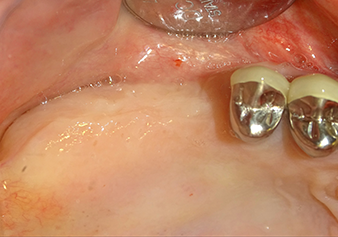

Una paziente di 49 anni, non fumatrice e con un'anamnesi priva di elementi rilevanti, è stata indirizzata al nostro studio di chirurgia orale per l'estrazione chirurgica del dente 16 ed il successivo impianto. Dopo l'estrazione, la paziente ha accusato dei lievi dolori causati dalla sinusite, motivo per cui abbiamo inizialmente aspettato sei mesi prima di procedere con l'intervento. L'altezza ossea residua in corrispondenza della posizione dell'impianto misurava 3-4 mm (Fig. 1 e 2).